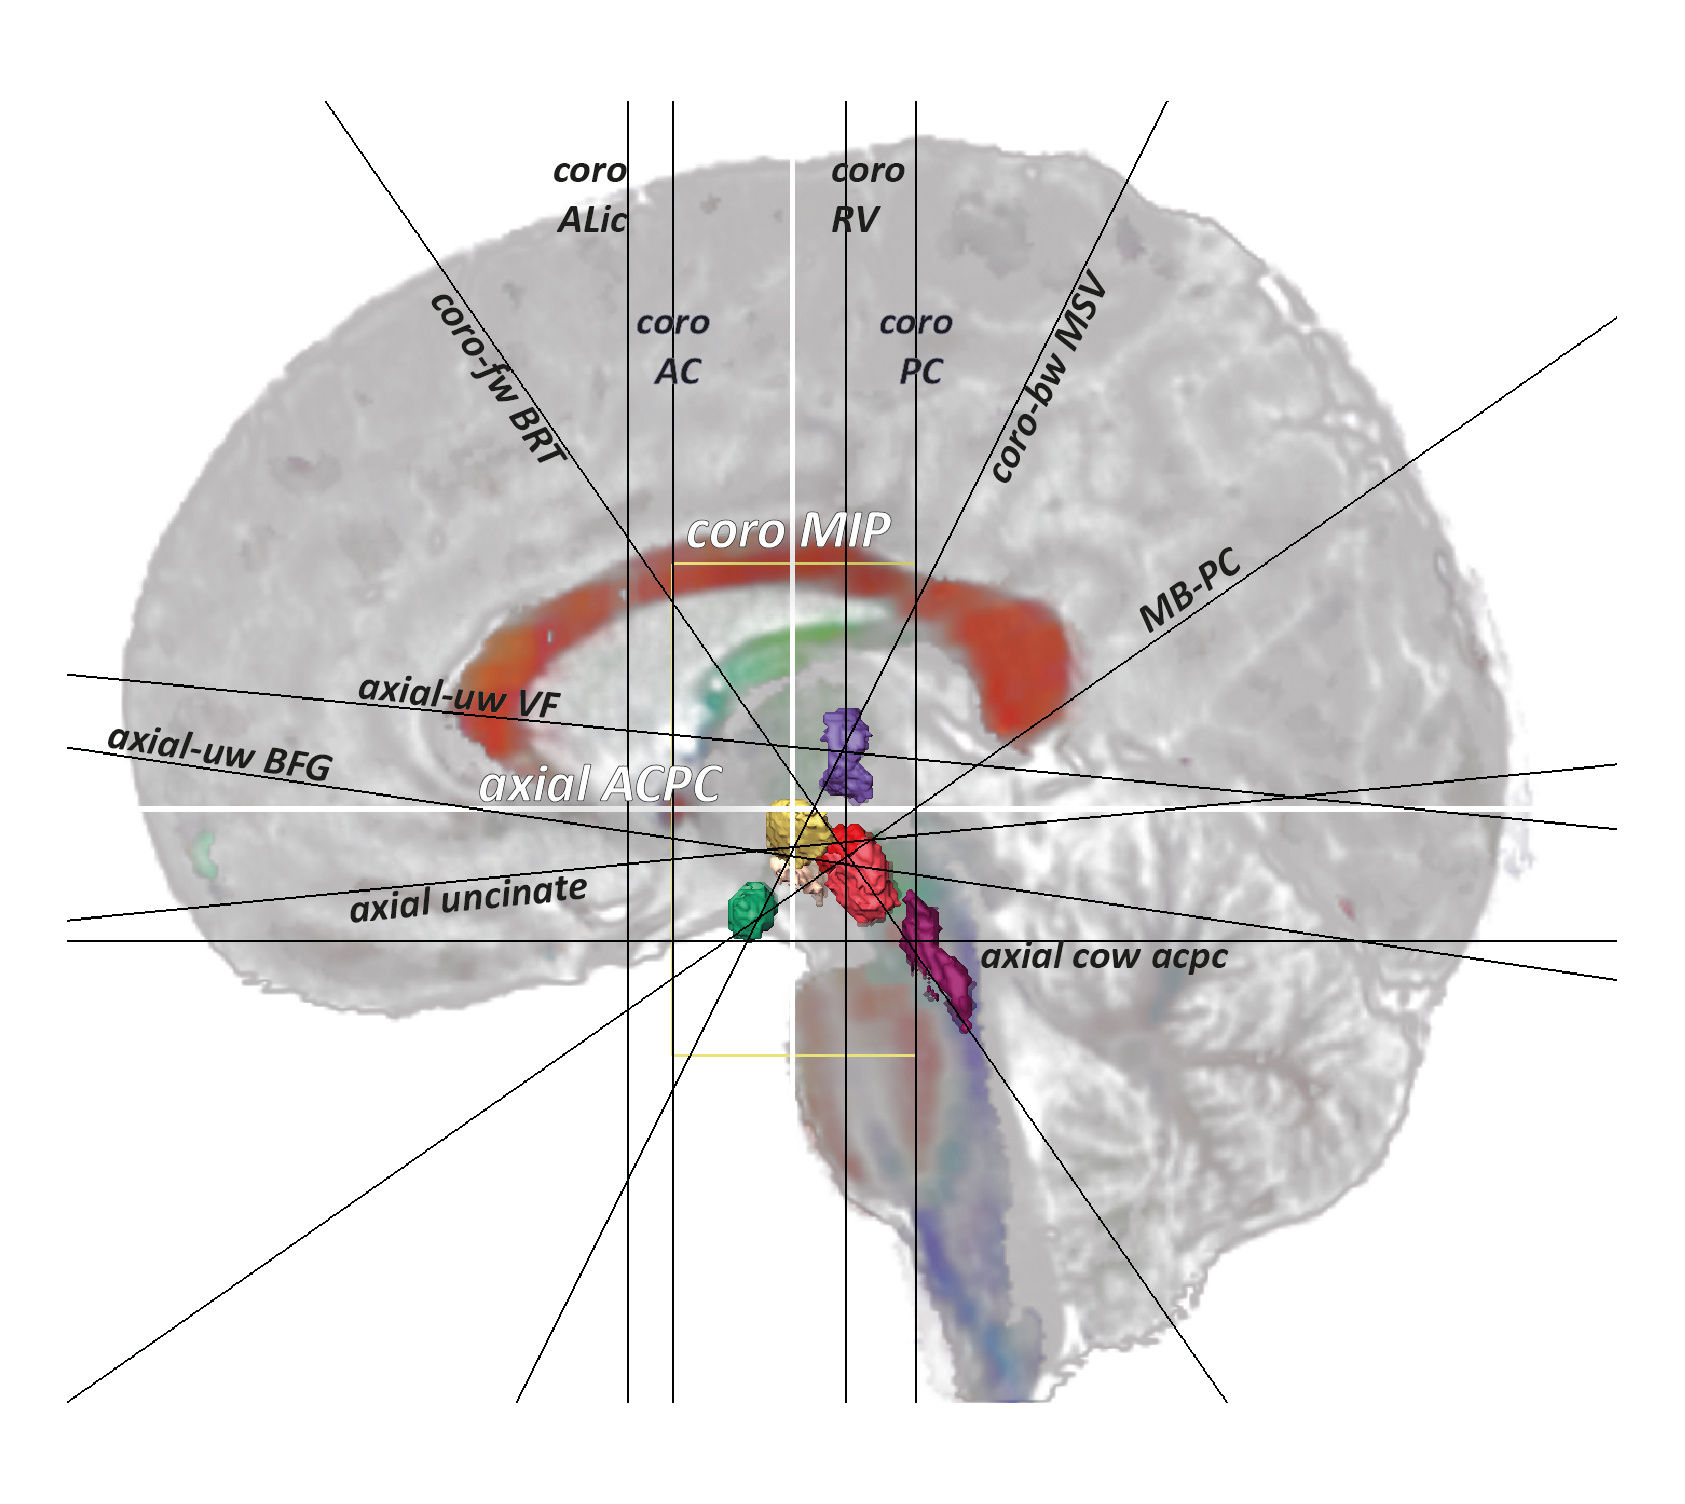

Thirteen reference slices were used to visually assess the topographic information in the DB-MA atlas These slices were selected from classical literature and oriented to show key structures. The two slices related to AC and PC served as geometrical frames of reference and enabled comparisons with current human stereotactic atlases.

Figure 1: Locations of reference slices (see manuscript for details; lateral view, midline slice merging WAIR and DCE): coro MIP, axial ACPC, coro-fw BRT, coro-bw MSV, coro ALic, coro AC, coro PC, coro RV, MB-PC axial-uw VF, axial-uw BFG, axial uncinate and the axial cow acpc; ACPC system (yellow box), y-length (ACPC length)=30 mm, z-height=60 mm; 3D views of red nucleus (red), mammillary body (green), subthalamic nucleus (yellow), ventral tegmental area (beige), nucleus ventrointermediate of thalamus (purple) and pedunculopontine nucleus (carmine).

Focused on the thalamo-subthalamic region, the analysis emphasized the nuclear-based and connectivity-based architectures, particularly landmarks like the subthalamic nucleus (STN), mammillary body (MB), red nucleus (RN), ventrointermediate nucleus of thalamus (Vim), peripeduncular nucleus (PPN), and ventral tegmental area (VTA). DEC maps identified main FT orientations, while tracing provided detailed structural insights on fascicles.